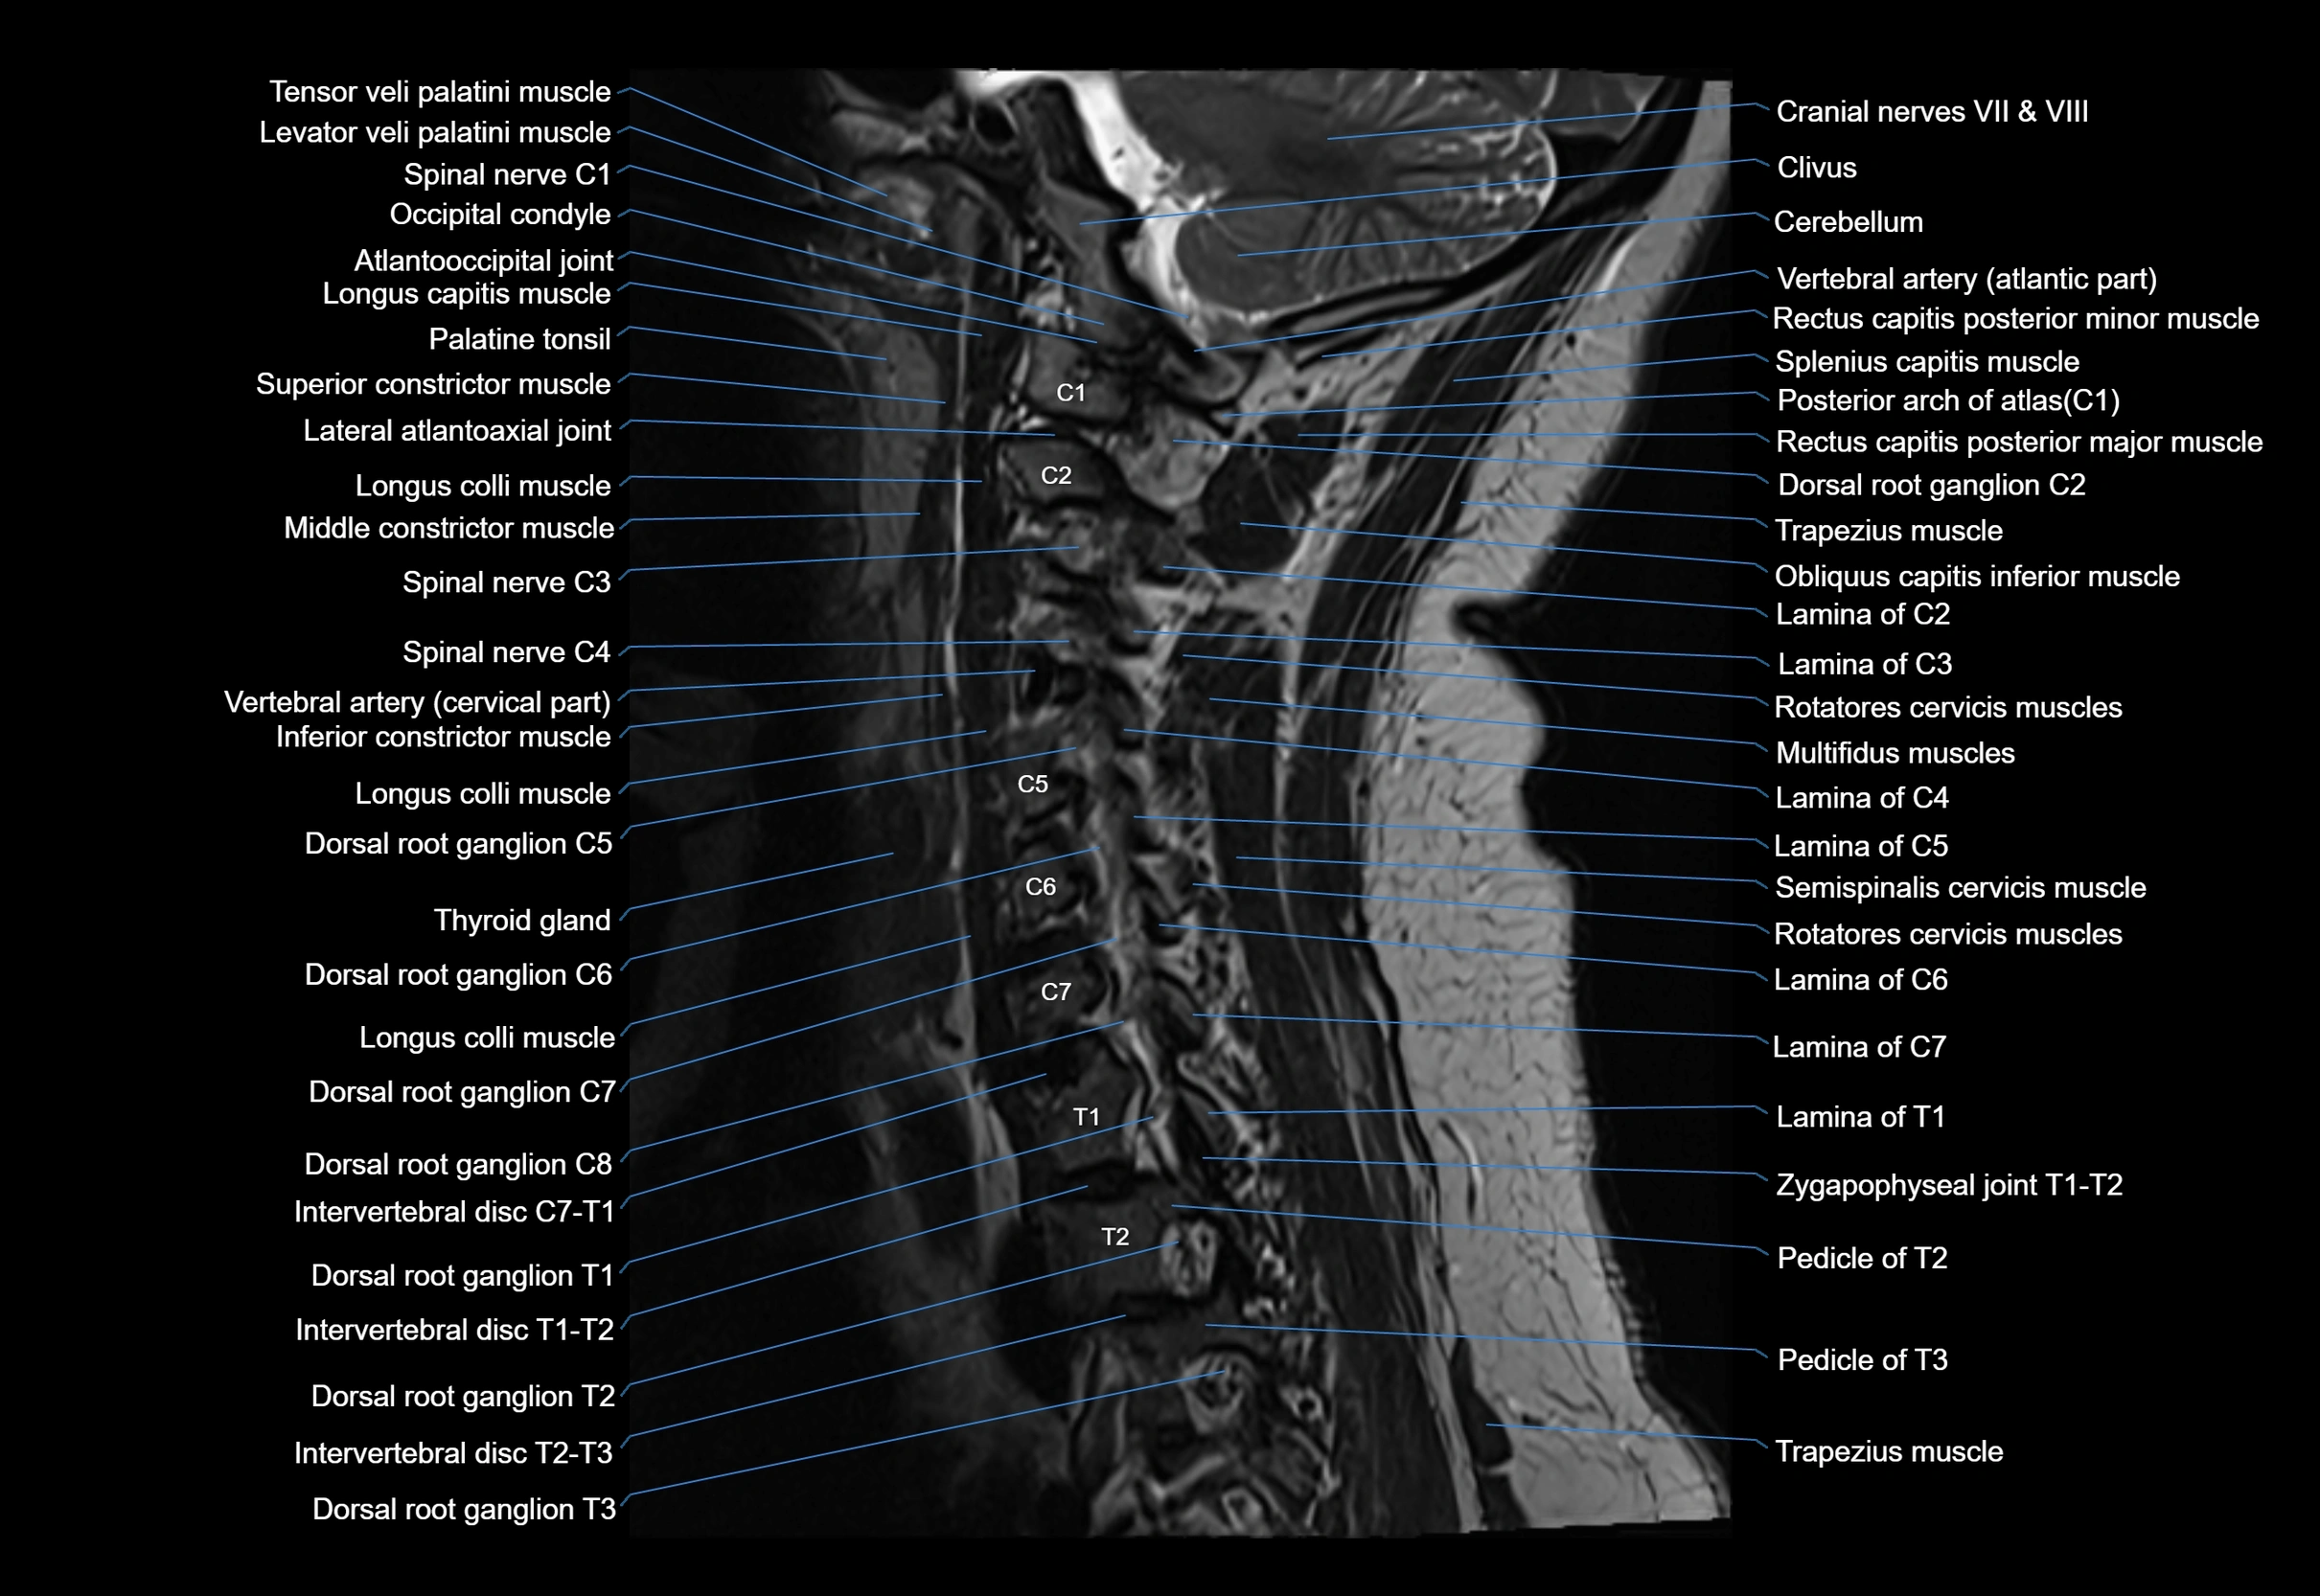

MRI appearance

T1-weighted images:

• Annular epiphysis: Low signal cortical rim at the vertebral margin

• Adjacent marrow: Intermediate-to-high signal in the vertebral body

• Disc interface: Clear delineation between bone and annulus

T2-weighted images:

• Annular epiphysis: Low signal intensity line

• Endplate cartilage (in younger patients): Intermediate signal

• Intervertebral disc: High signal nucleus pulposus

STIR:

• Annular epiphysis: Low signal cortical rim

• Adjacent marrow: Suppressed fat signal with preserved bony outline

• Utility: Highlights marrow and endplate interface in developing spine

MRI image

image